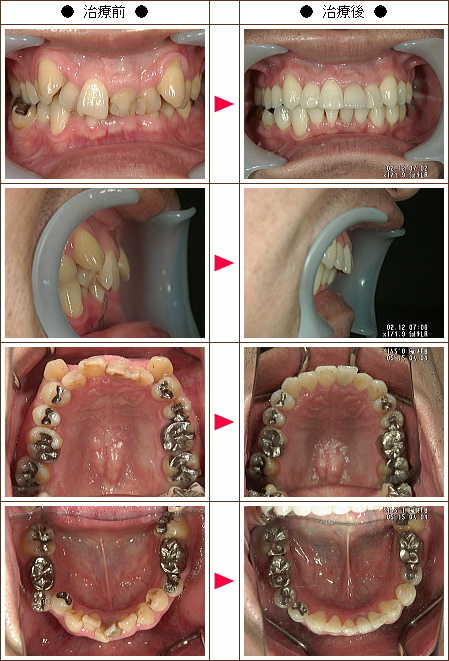

☆歯のデコボコ矯正症例[N.A様 48歳 男性]